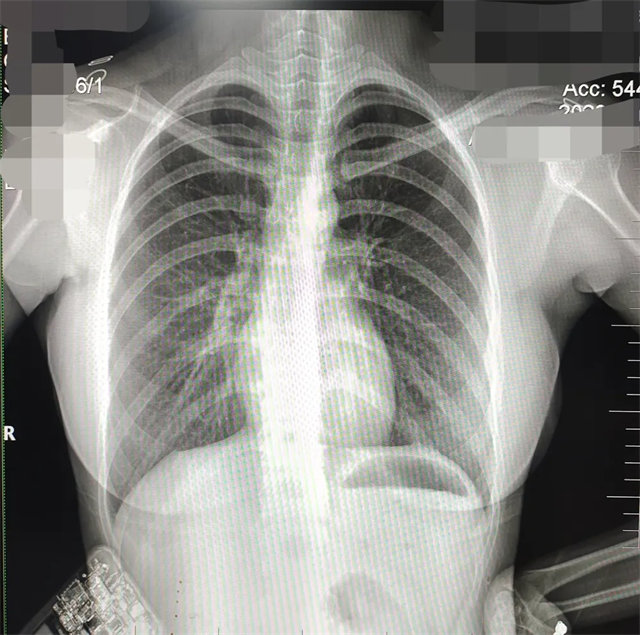

缺陷:兩肩胛骨未拉開(kāi)肺野之外,吸氣不完全,且存在金屬飾品遮擋。

解決:去除金屬飾品及內(nèi)衣后重新按標(biāo)準(zhǔn)體位攝片即可。